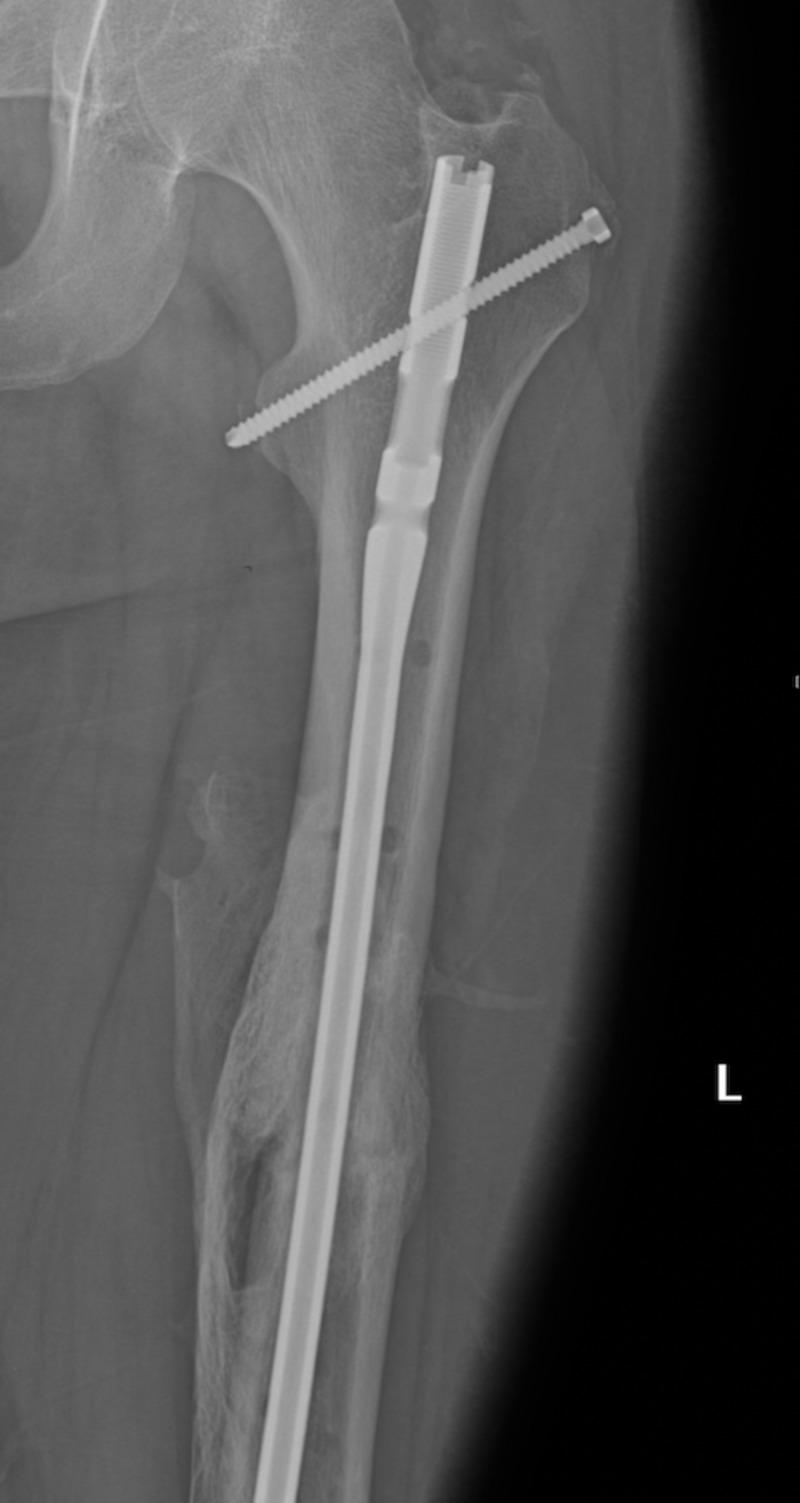

Fat embolism syndrome (FES) is a rare event following a traumatic injury, and its pathophysiologic mechanism continues to be elusive. Fat embolism syndrome generally occurs when a bone marrow fat enters the bloodstream resulting in a cascade of inflammatory response, hyper-coagulation, and an array of symptoms that generally begin within 24-48 hours. FES early symptoms include petechial rash, shortness of breath, altered mental status, seizures, fever, and may result in decreased urine output. The common etiologies of a fat embolism include long bone fractures, mainly femoral and pelvic fractures. There are multiple management methods described in the literature to help prevent FES and other long bone fracture complications from occurring. Although not universally adopted, the damage control orthopedics (DCO) has been the major management option for patients with a long bone fracture. DCO is entertained by provisional immobilization of patients with long bone fractures and those who are considered severely traumatized patients (STP). Thus, immobilization can help minimize the traumatic effect and the subsequent second hit by performing non-life saving surgical procedures. In this case, a patient with a transverse femur fracture suffered disconcerting symptoms of fat embolism prior to definitive femur repair. Hence, damage control orthopedics was entertained with a postponement of his femur repair to facilitate stabilization. The use of damage control orthopedics was successful in this patient with no long term complications.